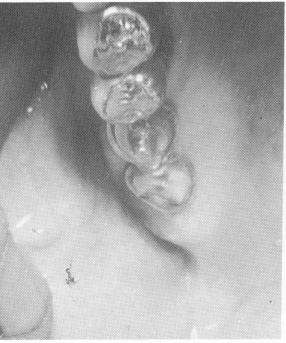

Fig. 15-64. The three pins were locked to each other and to the template with acrylic.

4 Acrylic locks upper pin implants  to each other and to template